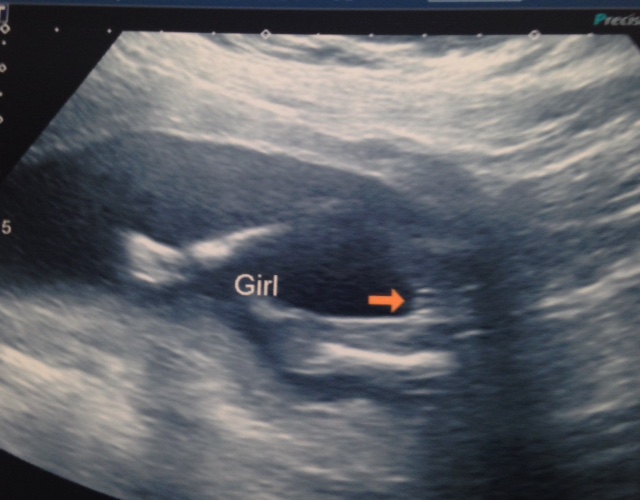

Im having a girl, after stopping my girl sway :)

Thought I would post, I have been trying for a girl for some years now on and off the LE diet (never 100%), after 2 years our doctor told us we had to turn to IVF to conceive, we decided not to as we have two healthy boys and after 8mths off the LE diet I fell pregnant accidently. I was eating lots of healthy foods (3 meals and snacks) at the time but had recently lost 5kg due to cardio and weights.I had also become vegetarian, I have always been overweight (and still quite heavy) and I think maybe the change in diet helped me to conceive a girl. I also have PCOS, I just wanted to say please don't lose hope, dreams can come true. Good Luck everyone :)Attachment 23585Attachment 23585